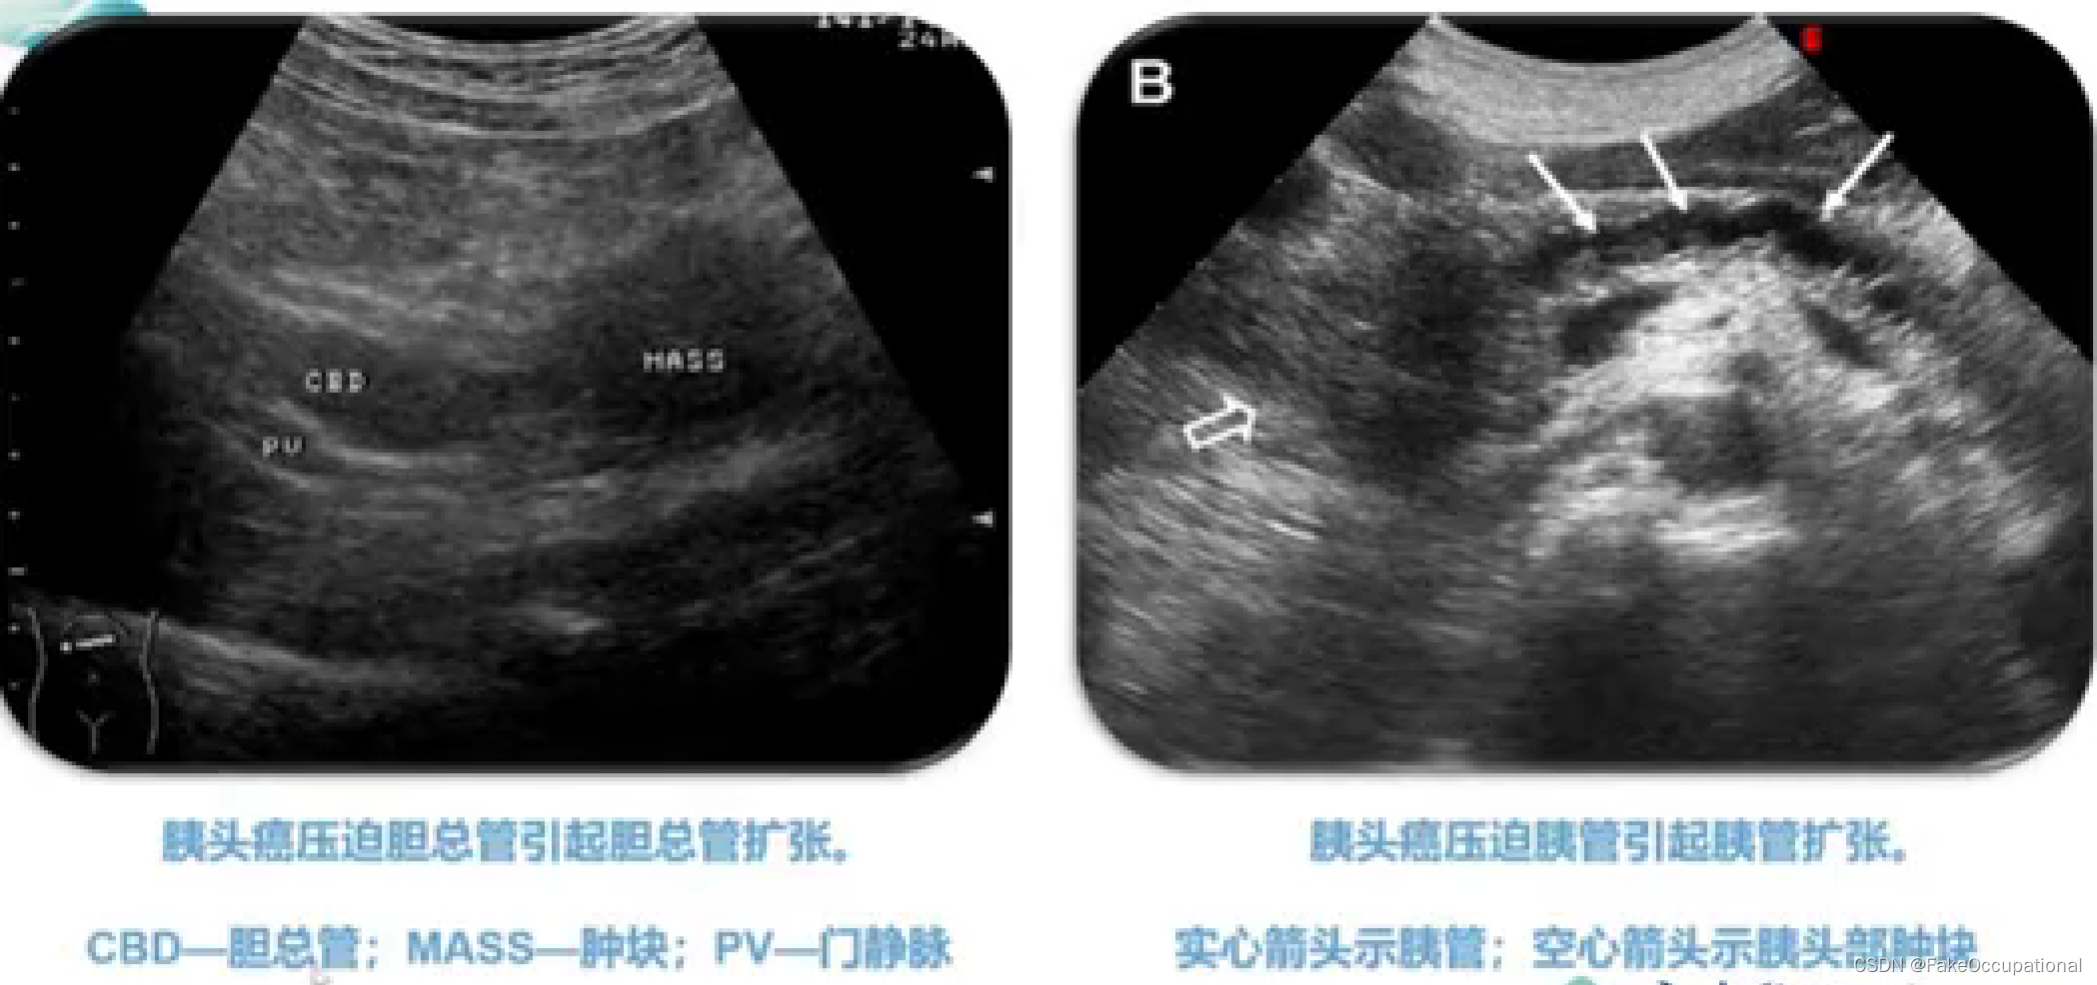

超声声像图: - 肝外胆道不同程度扩张

- (五)阻塞性黄疸的鉴别诊断

黄疽:血清内胆红素浓度增高。引起巩膜、皮肤、粘膜、体液、其他组织的黄染

临床分型:肝前性黄疸(溶血性黄痘、非溶血性)、肝性黄痘及肝后性黄疸(阻寒性黄疸)

胰腺解剖及正常声像图

胰腺肿瘤—胰岛细胞瘤、胰腺癌、壶腹癌